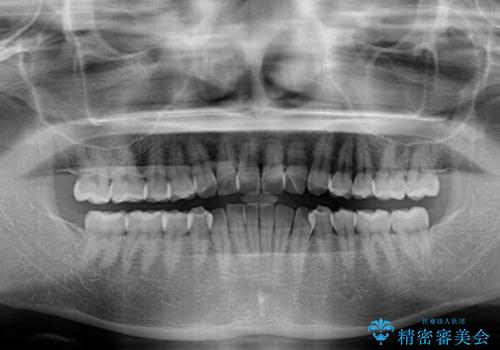

上下前歯のデコボコ ワイヤー装置で楽して改善

- 上下前歯のデコボコを気にして来院された患者様です。

ワイヤー矯正でもインビザラインでも、どの装置でも対応可能でしたが、安価で楽して素早く治療を終えたいとのことで、メタルブラケット装置による矯正治療を行うこととしました。

治療中は大きなトラブルもなく、予定の1年半でスムーズに治療を終えることができました。